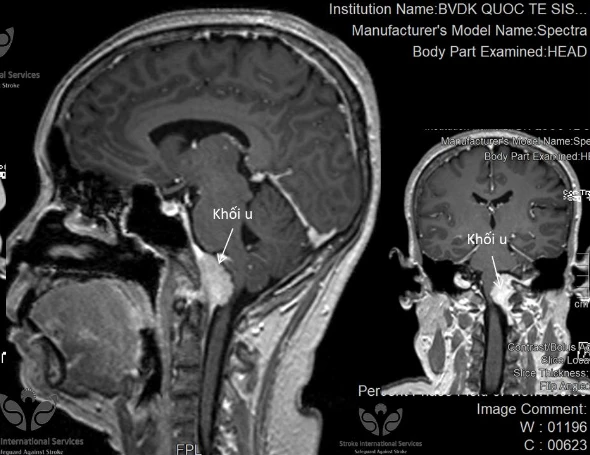

Kết quả chụp MRI 3 Tesla ghi nhận khối u nằm ở vị trí hiếm gặp. Ảnh: BVCC

Tại đây, bà N. được BS chỉ định chụp MRI 3 Tesla để tìm nguyên nhân chóng mặt. Kết quả cho thấy bà N. bị u màng não vùng mặt dốc xương đá-lỗ chẩm rất hiếm gặp. Sau khi tìm được nguyên nhân, các BS tiến hành điều trị bằng phương pháp can thiệp nội mạch. Hiện bà N. đã khỏi cơn chóng mặt triền miên.